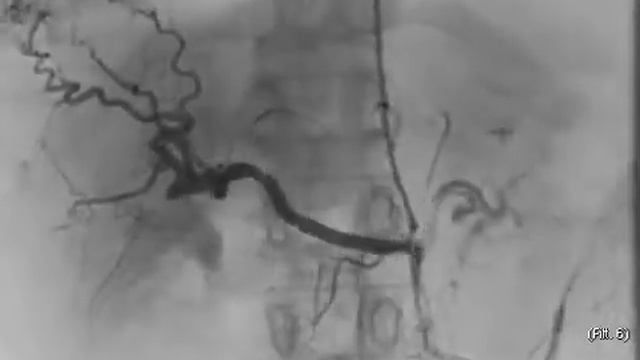

Брюшной полости ангиографии

Брюшной полости ангиографии 106 фото